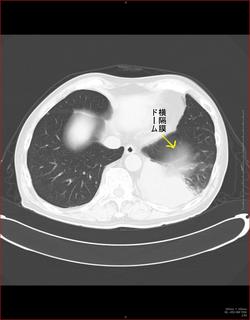

こちらを見て下さい。

わかりにくいかもしれませんが、このあたり。

気管が追いにくい、無くなっているようにも見えます。

CTで見ると…